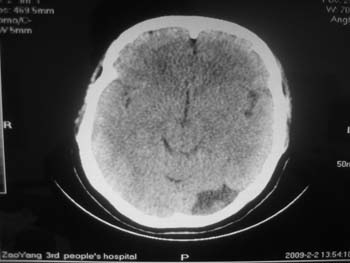

女。44岁,语言障碍三天,右侧上肢时而麻木。时而好转。其它图像未见异常。图像有点差请大家见谅。mg]/upload/forum/2009/02/0214453656449.jpg[/img]

双侧额叶密度低,考虑线束老化或脑梗塞?

左侧枕叶脑软化灶?

双侧额叶脑梗塞,左侧枕叶脑软化灶,

临近脑沟五增宽,考虑蛛网膜囊肿